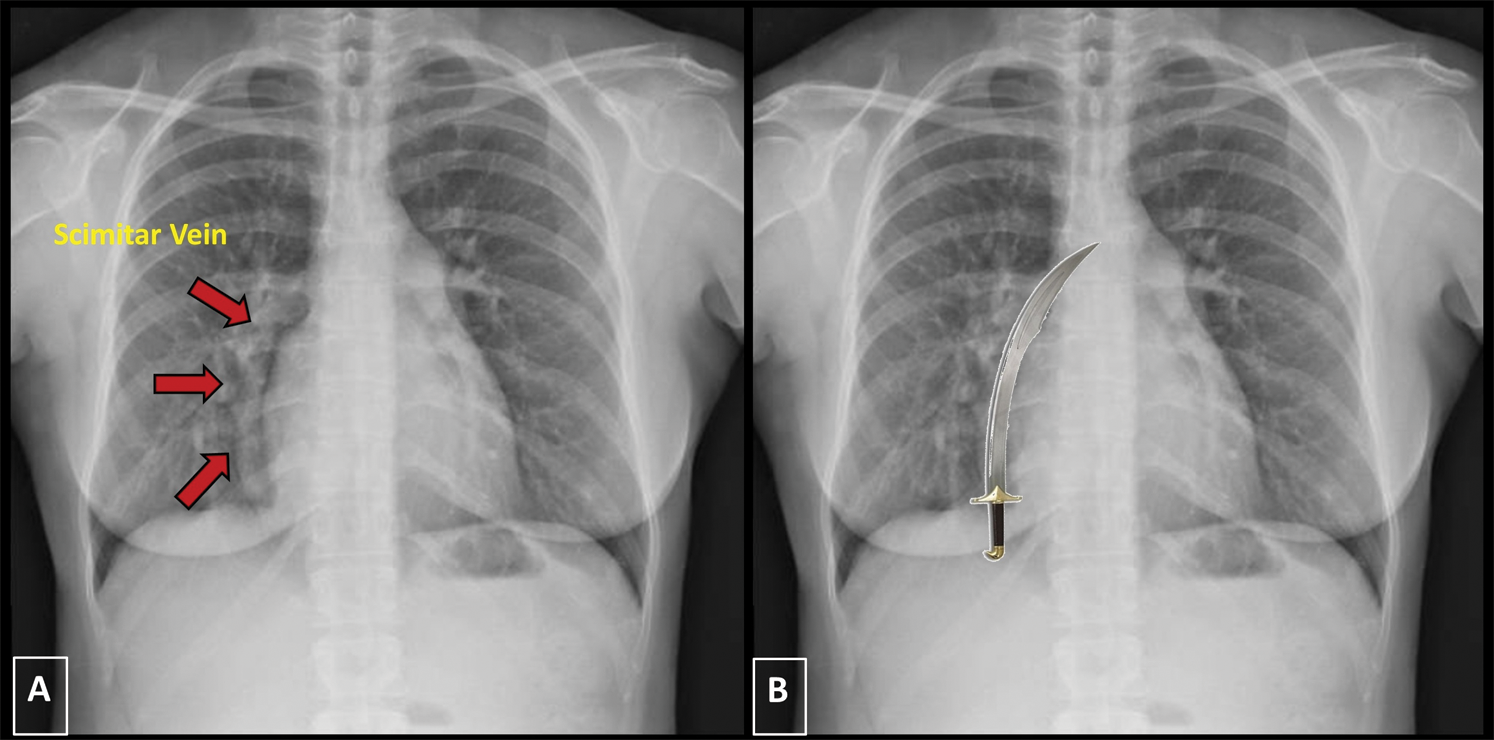

The chest X-ray showed the absence of pleuro-parenchymal lesions but revealed an abnormal, enlarged pulmonary vein running along the right heart border (Fig. 4).

Figure 4: Chest X-ray. Panel A. In a posteroanterior (PA) view the chest X-ray shows a curved tubular opacity along the right heart border (red arrows). Panel B. The anomalous, enlarged, draining vein has the shape of the typical Turkish sword, the scimitar

The scimitar syndrome is a rare CHD characterized by an abnormal pulmonary venous drainage into the IVC, variably associated with hypoplasia of the right lung and of the right pulmonary artery, systemic arterial supply for some part of the lung, atrial septal defect and heart dextroposition. The abnormal pulmonary vein is usually enlarged and runs along the right heart border, resembling the typical Turkish sword (“scimitar”) at chest X-ray (Fig. 4) [5]. Its clinical presentation varies from severe congestive heart failure to mild symptoms. In our patient, RV enlargement secondary to acute PE was excluded after a normal D-Dimer dosage, and CAD was ruled out after performing a coronary CT, according to the current guidelines and the pre-test probability for CAD [6]. ARVD was rejected as cause of RV enlargement because the current diagnostic criteria [7] were not fulfilled. CHD are often underdiagnosed in adult; in case of signs of RV overload and absence of septal defects an anomalous return of pulmonary vein must be investigated. Echocardiographic examination is crucial in the diagnostic pathway of these patients, although PAPVR is a frequently missed diagnosis at echocardiography. In addition to already consolidated conventional echocardiographic indices, STE have demonstrated to have a good reproducibility and capability to detect even subtle myocardial dysfunction [8]. A novel diagnostic tool, MWI, is capable to provide additional information on LV function with good accuracy, taking also into account load condition [3]. This index has demonstrated to detect even subtle myocardial disfunction in several clinical setting [9] and could be used in the routinely evaluation of patients with CHD to better evaluate myocardial performance. Myocardial work indices were completely normal in our patient, confirming a preserved left ventricular function already assessed by 2D ejection fraction and global longitudinal strain. However, as the use of MWI in this context has not been validated yet, this finding should be considered purely informative and cannot represent a relevant element to direct clinical management. Atrial strain is often overlooked during standard echocardiographic examination. However, LA strain has demonstrated to be an indirect index of LV filling pressure, diastolic dysfunction and to predict worse prognosis [10]; Right atrial function estimated by STE plays a crucial role in case of RV overload; in fact, a preserved RA contractility is essential in maintaining a proper RV output in the presence of elevated diastolic filling pressures. Identifying the failure of the right atrium in compensating the pressure overload of the RV, that often predicts RV dysfunction, might allow to better comprehend the stage of the disease and the hemodynamic of the patient. However, its diagnostic and prognostic role in patients with anomalous venous return is not yet well defined yet, despite its association with worse prognosis in several clinical setting including CHD [11]. Multi-chamber strain is a useful tool capable to provide crucial information on myocardial function, providing reliable prognostic information and holding a wide range of potential clinical applications in patients with CHD.